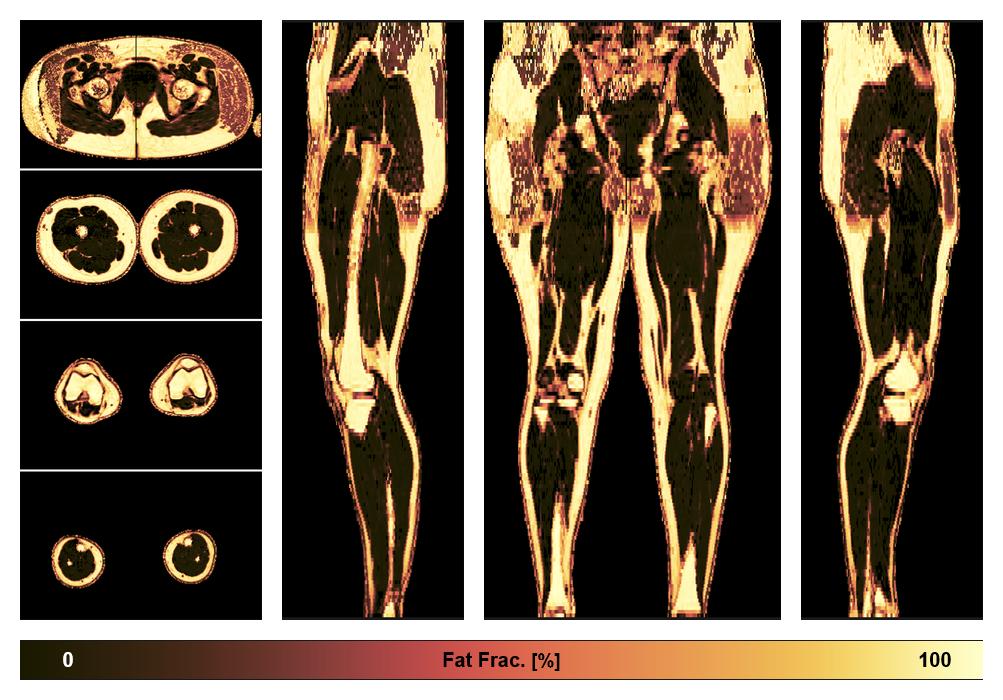

• Fat fraction

The fat fraction of the lower extremity obtained from the dixon reconstruction for muscle water fat quantification.